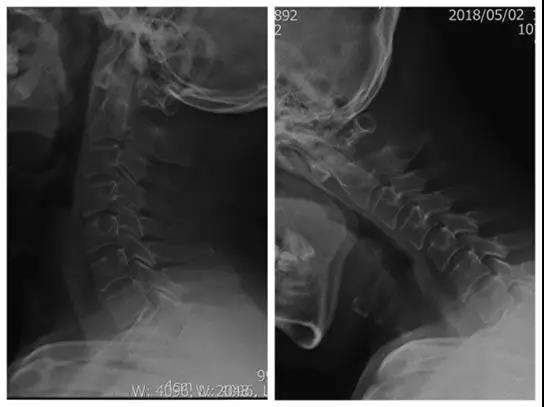

术前X线正、侧位片

患者:男,35岁

主诉:外伤后肩颈部疼痛伴左上肢放射痛、麻木10天

现病史:患者因10天前从高处坠落致肩颈部疼痛,左上肢放射痛、麻木

诊断:颈椎病(C6/7)